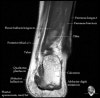

발목 관절의 MRI 단면 영상

- Sagittal section

Bones and marrow

Joint fluid

Talar dome

Subtalar joints

Achille's tendon

Sinus tarsi

Plantar fascia